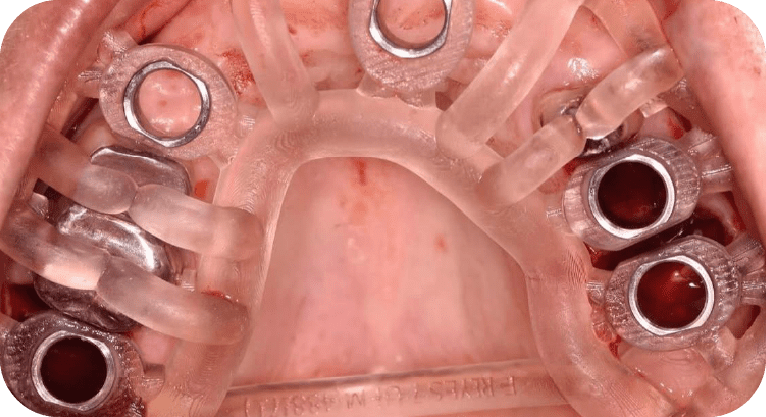

Paciente femenino, “52” años

Tratamiento: All of 4

La paciente acudió a la clínica tras perder varios dientes superiores por caries, utilizando una prótesis removible que le resultaba incómoda; deseaba una solución fija, por lo que se le realizó una rehabilitación completa con técnica All-on-4, colocando 4 implantes dentales que soportan una prótesis fija, devolviéndole la funcionalidad, seguridad y una sonrisa natural de forma permanente.